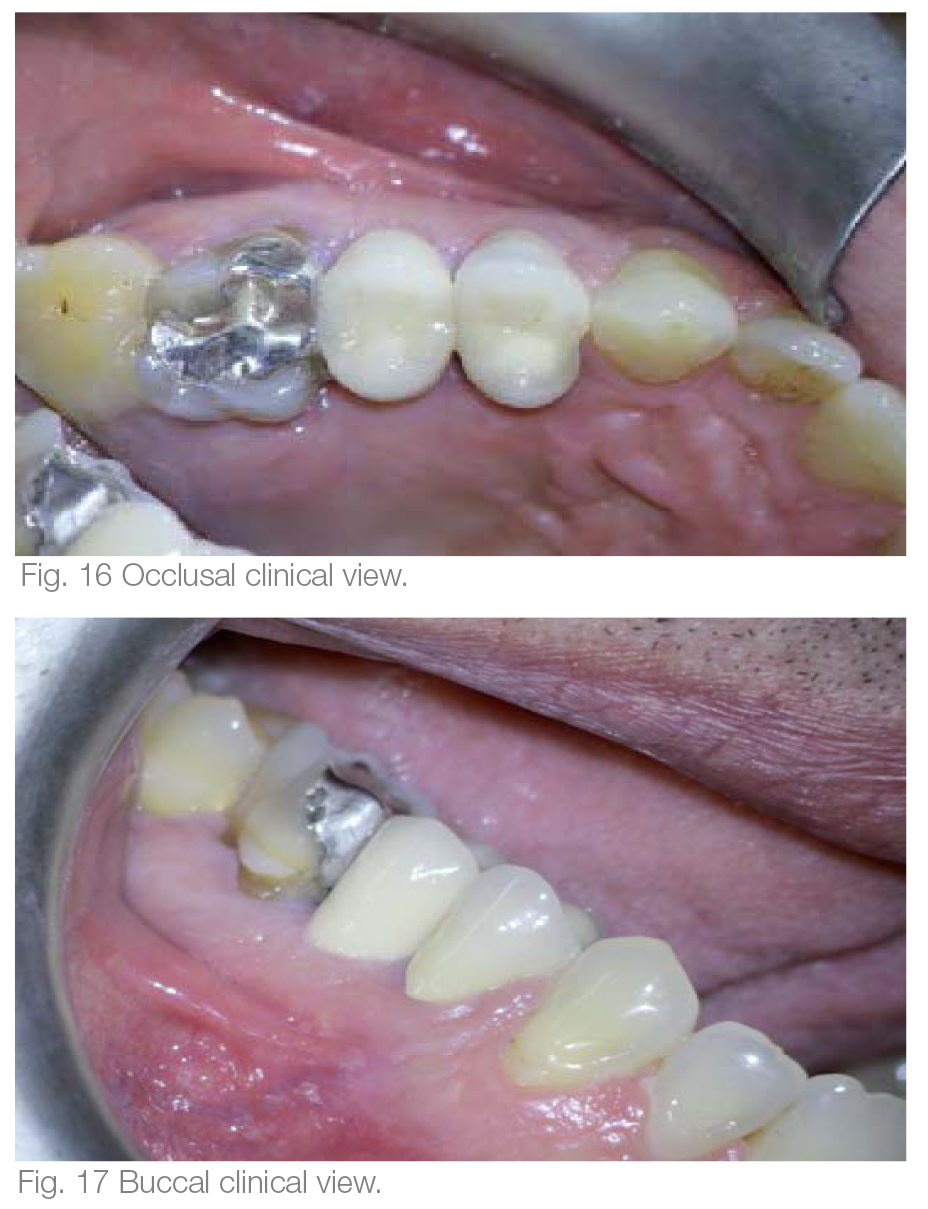

The tooth was restored with a fiber post, a composite built up and a PFM crown. In the final radiographic image of the tooth right after the RCT, the lateral ports of exit could be visualised (Fig. 14). One year after the treatment, the follow-up radiograph revealed complete healing. The nonabsorbable GuttaFlow 2 could be detected unaltered in the lateral portals of exit (Fig. 15). The buccal and occlusal clinical view of the tooth and soft tissues can be seen in Figures 16 and 17.